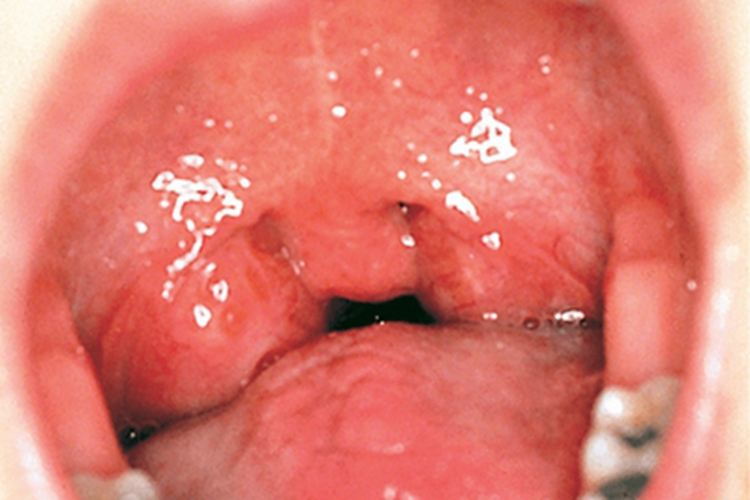

急性扁桃体发炎可以表现为患者两侧扁桃体红肿,像两个大肉球,表面光滑发亮,触之有弹性,按压有痛感。吞咽食物时,自觉局部痛感加剧。